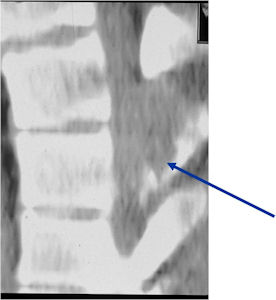

Plain X-rays:

- Geographic, circumscribed lesion usually around 5cm in size.

- There may be expansion of bone, cortical thinning and cortical breakthrough. A soft tissue mass may accompany this lesion but the soft tissue component is usually contained by the periosteum.

- The periosteum remains intact around the soft tissue component. Might need a CT scan to detect the subtle calcification (Egg Shell Rim of Calcification) associated with an intact periosteal reaction

- The lesion may be entirely radiolucent but usually shows some degree of mineralization. Mineralization may appear stippled like cartilage but do not see chondroid pathologically. Mineralization is sometimes better detected on a CT scan rather than an x-ray.

- Usually less surrounding sclerosis than an osteoid osteoma.